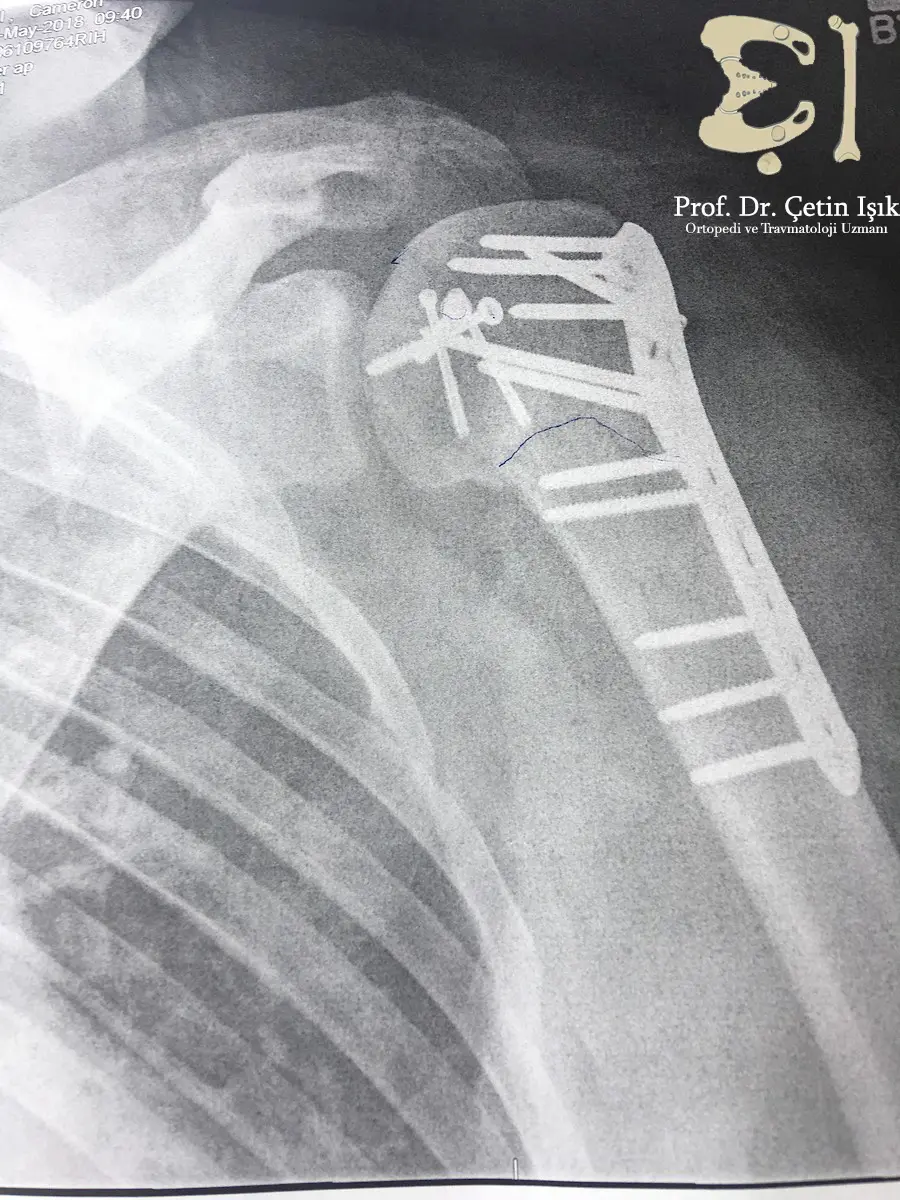

From drcetinisik.com

Shoulder fracture treatment the joint returns to normal Dr. What's Shoulder Fracture Screws A shoulder fracture repair may include plates and screws as shown here. Shoulder dislocations can involve any of. If your shoulder is in many pieces, the doctor might recommend a shoulder replacement instead. Internal fixation is a surgical procedure used to internally set and stabilize fractured bones. The options for surgery include realigning the bone fragments and holding them in. Shoulder Fracture Screws.